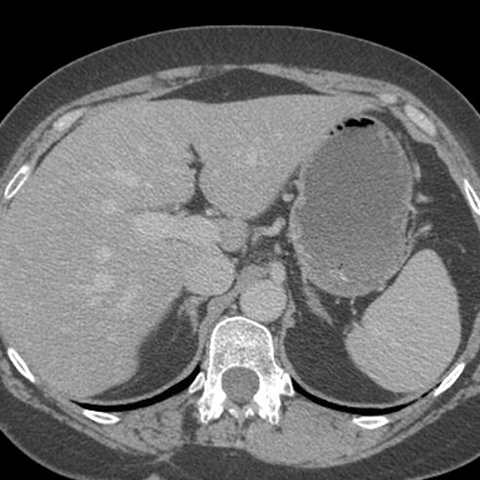

Normal Stomach, axial CT [1 of 4]